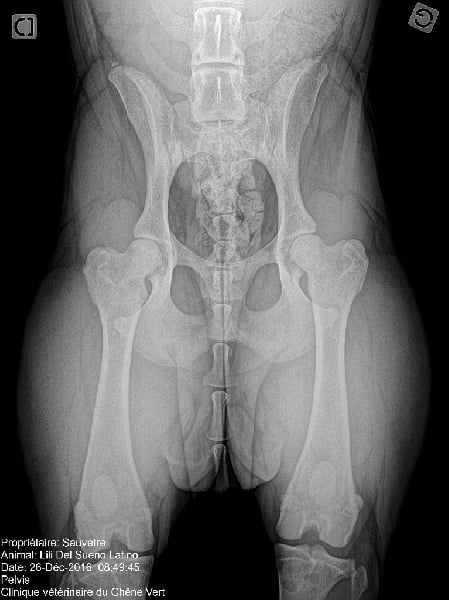

Compte rendu officiel Dysplasie coxo-fémorale

ADN : identifiée + filiation parenté BAER : +/+ Dysplasie coxo-fémorale : A/A officiel Dysplasie des coudes : 0/0 officiel |